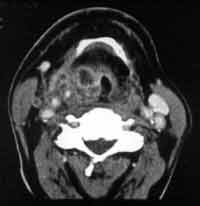

Рис. 1. КТА сосудов шеи у больного М., 55 лет раком гортани.

Увеличенные (метастазы) лимфоузлы в области бифуркации общей сонной артерии с компрессией внутренней яремной вены. Расширение поверхностной яремной вены, осуществляющей коллатеральный кровоток.